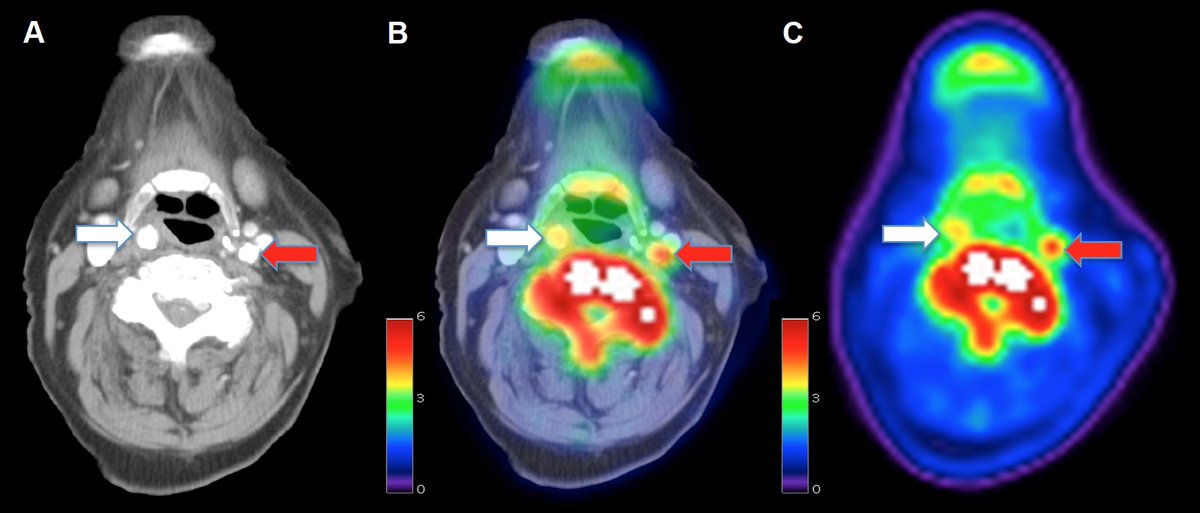

What is going on here? I'll be presenting our PET work at 5.30pm, MP 29. Why not come and find out more? #ISC2017 @DunhillMedical @CamStroke